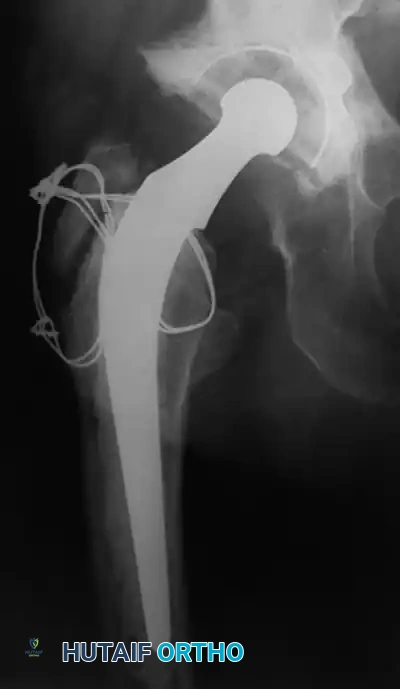

Associated Surgical & Radiographic Imaging